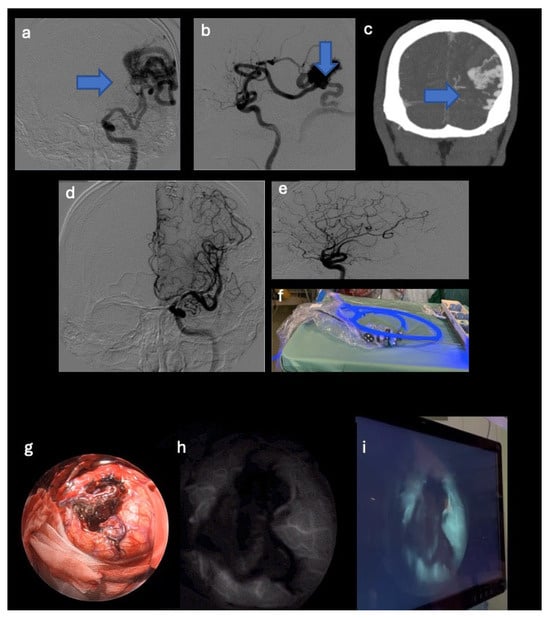

- A 44-year-old female patient with a right middle cerebral artery aneurysm (M1-M2 union) with a diameter of 1 cm, a history of headaches. The patient underwent clipping of the aneurysm neck (see Figure 2).

3.2.2. CASE Number 4

| 4 | 44 | F | Headache | Right middle cerebral artery aneurysm (M1-M2 union) with a diameter of 1.1 cm | Clipping of the aneurysm neck | Neurologically intact, total exclusion of the aneurysm, and no bleeding events. |